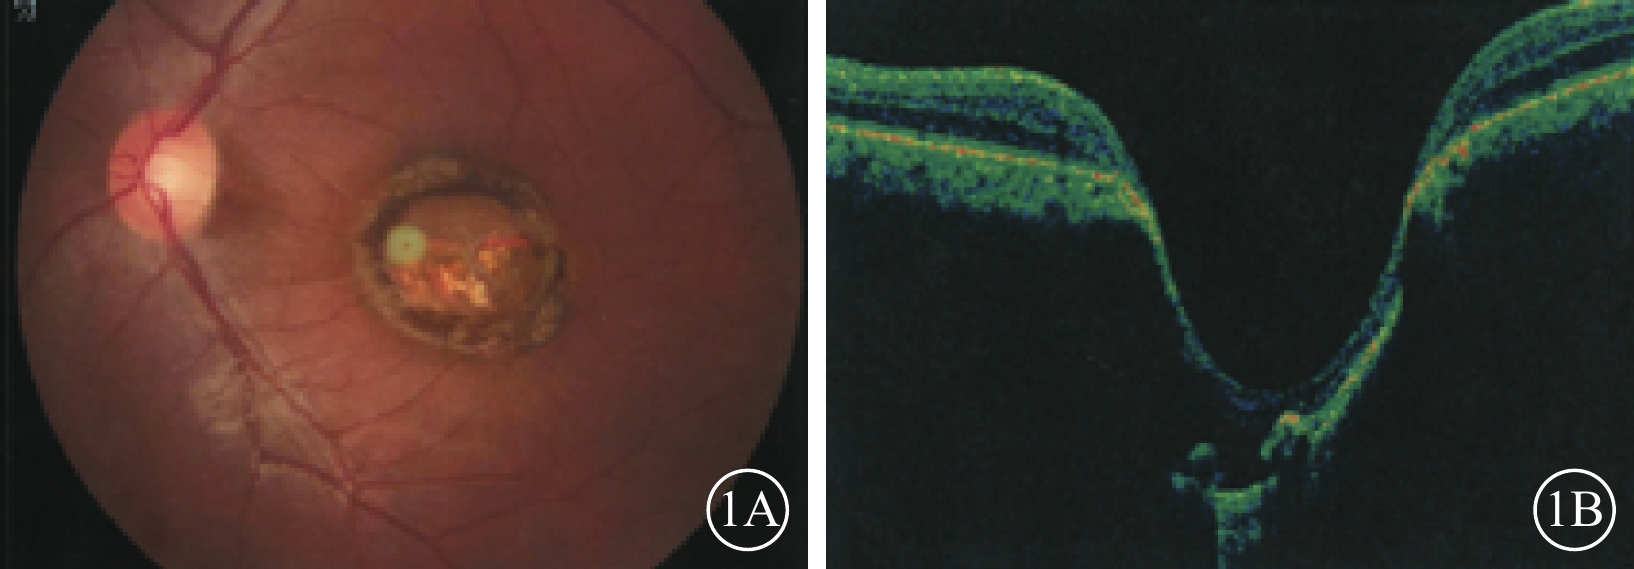

例1 患者男,24歲。因自幼雙眼視力差于2016年12月來我院眼科就診。父母非近親結婚,除其兄自幼雙眼視力差外,余家族史無特殊。否認夜盲及全身病史、母親孕期感染及藥物使用史。眼科檢查:雙眼眼位正,無眼球震顫。雙眼視力0.1,均不能矯正。右眼眼壓18 mmHg(1 mmHg=0.133 kPa),左眼眼壓19 mmHg。雙眼瞳孔對光反射遲鈍,其余眼前節檢查正常。右眼視盤邊界清楚,顏色基本正常,杯盤比(C/D)=0.3;視網膜平復,黃斑區可見約1/5個視盤直徑(DD)大小的橫橢圓形缺損區,其邊界清晰,中間透見脈絡膜血管。左眼視盤邊界清楚,顏色淡黃,C/D=0.3;視網膜平復,黃斑區可見約1.5 DD大小的類圓形缺損區(圖1A);其邊界清晰,凹陷深,中間可見灰白色鞏膜組織,透見脈絡膜大血管,病變邊緣可見色素沉著。光相干斷層掃描(OCT)檢查,右眼黃斑缺損區視網膜外層結構缺失,橢圓體帶缺損,視網膜色素上皮(RPE)層完整;左眼黃斑缺損區視網膜脈絡膜組織隨鞏膜組織局限性向外凹陷,凹陷區域內視網膜神經上皮層明顯變薄,部分缺損,其下方可見淺脫離(圖1B)。基因檢查:患者攜帶下列雜合突變:(1)RP9 c. 448C>T,p. R150*;(2)VSX1 c. 479G>T,p. G160V;(3)CEP290 c. 3573+3A>G;(4)CEP290 c. 366A>G,p. K122K。診斷:雙眼先天性黃斑缺損(色素型)。

圖1

例1患者左眼彩色眼底、OCT像。1A. 彩色眼底像,黃斑區可見一大小約1.5 DD的類圓形缺損區,邊界清晰,病灶邊緣存在色素沉著;1B. OCT像,黃斑缺損區視網膜脈絡膜組織局限性向外凹陷,凹陷區域內視網膜神經上皮層可見部分缺損

圖1

例1患者左眼彩色眼底、OCT像。1A. 彩色眼底像,黃斑區可見一大小約1.5 DD的類圓形缺損區,邊界清晰,病灶邊緣存在色素沉著;1B. OCT像,黃斑缺損區視網膜脈絡膜組織局限性向外凹陷,凹陷區域內視網膜神經上皮層可見部分缺損

例1 患者男,24歲。因自幼雙眼視力差于2016年12月來我院眼科就診。父母非近親結婚,除其兄自幼雙眼視力差外,余家族史無特殊。否認夜盲及全身病史、母親孕期感染及藥物使用史。眼科檢查:雙眼眼位正,無眼球震顫。雙眼視力0.1,均不能矯正。右眼眼壓18 mmHg(1 mmHg=0.133 kPa),左眼眼壓19 mmHg。雙眼瞳孔對光反射遲鈍,其余眼前節檢查正常。右眼視盤邊界清楚,顏色基本正常,杯盤比(C/D)=0.3;視網膜平復,黃斑區可見約1/5個視盤直徑(DD)大小的橫橢圓形缺損區,其邊界清晰,中間透見脈絡膜血管。左眼視盤邊界清楚,顏色淡黃,C/D=0.3;視網膜平復,黃斑區可見約1.5 DD大小的類圓形缺損區(圖1A);其邊界清晰,凹陷深,中間可見灰白色鞏膜組織,透見脈絡膜大血管,病變邊緣可見色素沉著。光相干斷層掃描(OCT)檢查,右眼黃斑缺損區視網膜外層結構缺失,橢圓體帶缺損,視網膜色素上皮(RPE)層完整;左眼黃斑缺損區視網膜脈絡膜組織隨鞏膜組織局限性向外凹陷,凹陷區域內視網膜神經上皮層明顯變薄,部分缺損,其下方可見淺脫離(圖1B)。基因檢查:患者攜帶下列雜合突變:(1)RP9 c. 448C>T,p. R150*;(2)VSX1 c. 479G>T,p. G160V;(3)CEP290 c. 3573+3A>G;(4)CEP290 c. 366A>G,p. K122K。診斷:雙眼先天性黃斑缺損(色素型)。

圖1

例1患者左眼彩色眼底、OCT像。1A. 彩色眼底像,黃斑區可見一大小約1.5 DD的類圓形缺損區,邊界清晰,病灶邊緣存在色素沉著;1B. OCT像,黃斑缺損區視網膜脈絡膜組織局限性向外凹陷,凹陷區域內視網膜神經上皮層可見部分缺損

圖1

例1患者左眼彩色眼底、OCT像。1A. 彩色眼底像,黃斑區可見一大小約1.5 DD的類圓形缺損區,邊界清晰,病灶邊緣存在色素沉著;1B. OCT像,黃斑缺損區視網膜脈絡膜組織局限性向外凹陷,凹陷區域內視網膜神經上皮層可見部分缺損